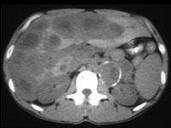

- 多项选择题男,37岁, 阵发性高血压1月余,结合所示图像, 最可能的诊断是 ( )

A、左侧肾上腺癌

B、左侧恶性嗜铬细胞瘤

C、左侧肾上腺转移癌

D、肝转移癌

E、原发性肝癌